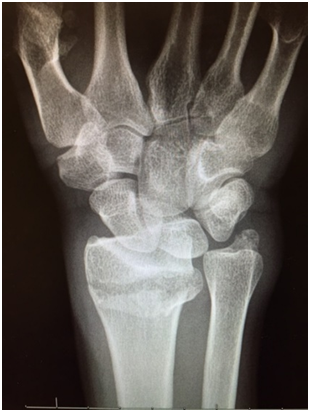

Consent information for wrist fracture surgery

This is a common injury resulting from a fall onto an outstretched hand. It can often occur as a result of low energy trauma in the elderly and higher energy injuries are seen in the younger population. The treatment can be operative (surgical fixation) and non-operative (treatment in plaster) depending on the type of fracture. Your surgeon will advise on the type of treatment of your fracture.